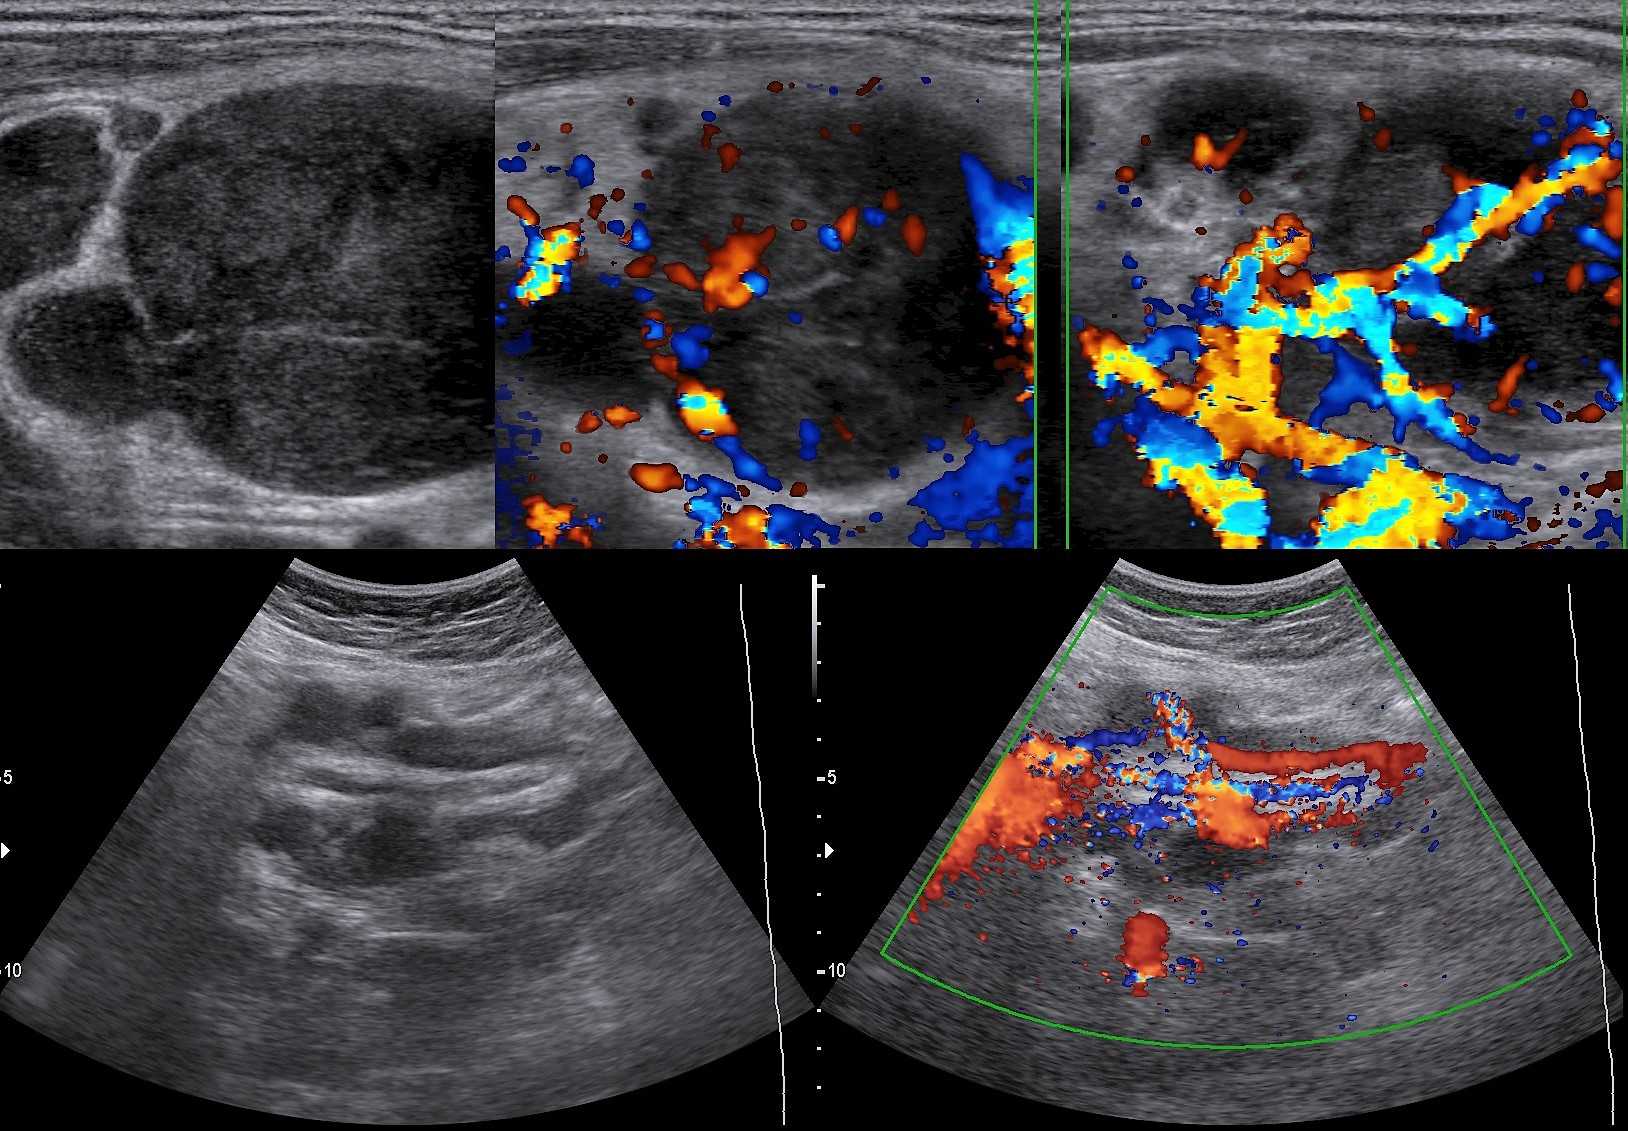

Вступая в борьбу с инфекцией лимфоузлы воспаляются. Воспалённые лимфоузлы стремительно «растут» в начале болезни и быстро «сдуваются» при выздоровлении. На УЗИ лимфоузел увеличен за счет корковой и околокорковой зоны, гипоэхогенный по периферии и гиперэхогенный в центре, форма овальная, контур четкий, кровоток только в воротах или отсутствует. Если воспаление переходит в окружающую клетчатку (периаденит), то может сформироваться абсцесс.

Рисунок. У детей с ОРВИ на УЗИ увеличенные шейные лимфоузлы с сохранной архитектурой — овальной формы, контур четкий и ровный, гипоэхогенные по периферии с гиперэхогенным центром. Заключение: Лимфаденопатия шейных лимфоузлов.

Рисунок. На УЗИ лимфоузлы увеличены, овальной формы, четкий и ровный контур, эхогенность пониженная, корковая зона несколько расширена, центральный рубчик видно отчетливо; кровоток в воротах усилен, сосуды расположены правильно — расходятся радиально, подкапсульный кровоток не определяется. Заключение: Лимфаденопатия с признаками высокой степени активности.

Рисунок. Женщина жалуется на «опухоль» в подмышке и на локте. Неделю назад повздорила с соседской кошкой. На УЗИ подмышечный (сверху) и локтевые (снизу) лимфоузлы увеличены, округлой формы, выраженная гиперплазия корковой и околокорковой зоны, гиперэхогенный центральный рубчик сохранен; кровоток заметно усилен, сосуды расположены правильно — радиально. Заключение: Лимфаденопатия с признаками высокой степени активности. При болезни кошачьей царапины на месте укуса или царапины образуются небольшие гнойнички и одновременно воспаляются близкие лимфоузлы. Один или группа лимфоузлов увеличиваются в размерах до 5-10 см, становятся болезненными, уплотняются. Через 2-4 недели происходит самоизлечение. Иногда образуются абсцессы и свищи.